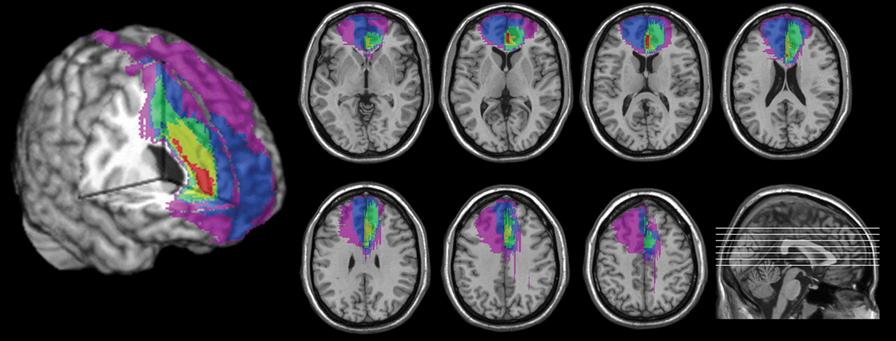

Thanks to brain imaging technology like fMRI, scientists have discovered that mental simulation activates many of the same neural systems involved in real experiences In other words, when you imagine practicing a skill or navigating a future situation, your brain partially rehearses that event as if it were real

A key set of studies by Addis, Wong, and Schacter (2007) found that episodic future thinking— imagining a personal future event relies on the same brain structures used for remembering the past. These include the hippocampus (involved in memory formation and scene construction), the medial prefrontal cortex (linked to self-referential thinking and goal setting), and the posterior cingulate cortex (involved in evaluating mental representations) This overlap suggests that our brains use memory not just to recall, but to construct and simulate possibilities

In sports psychology, this finding is significant Studies using motor imagery show that imagining a physical action activates the supplementary motor area, premotor cortex, and even the primary motor cortex; regions responsible for actual movement execution (Decety & Grèzes, 2006) While the signal is weaker than when acting itself, the pattern is remarkably similar This means athletes who mentally rehearse a routine are not only preparing psychologically they're also fine-tuning the brain’s motor programs

Even emotional experiences can be simulated. According to a 2015 study published in Nature Communications, participants who imagined future emotional events (such as receiving praise or experiencing rejection) showed increased activity in the amygdala and ventromedial prefrontal cortex, areas associated with emotional processing and regulation. This suggests that imagination allows us to emotionally “test-drive” situations before they happen